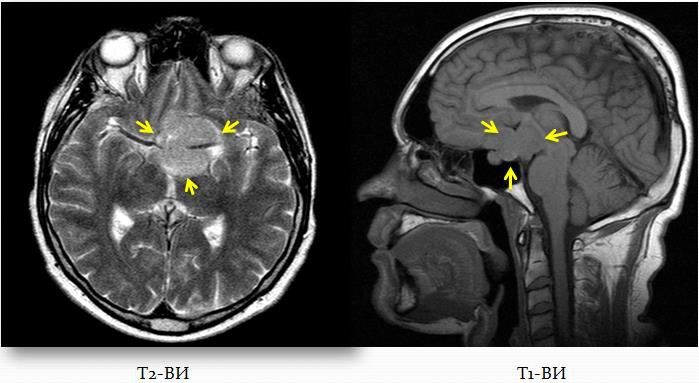

Объемное образование селлярной области с интра-латеро- и супраселлярным ростом: